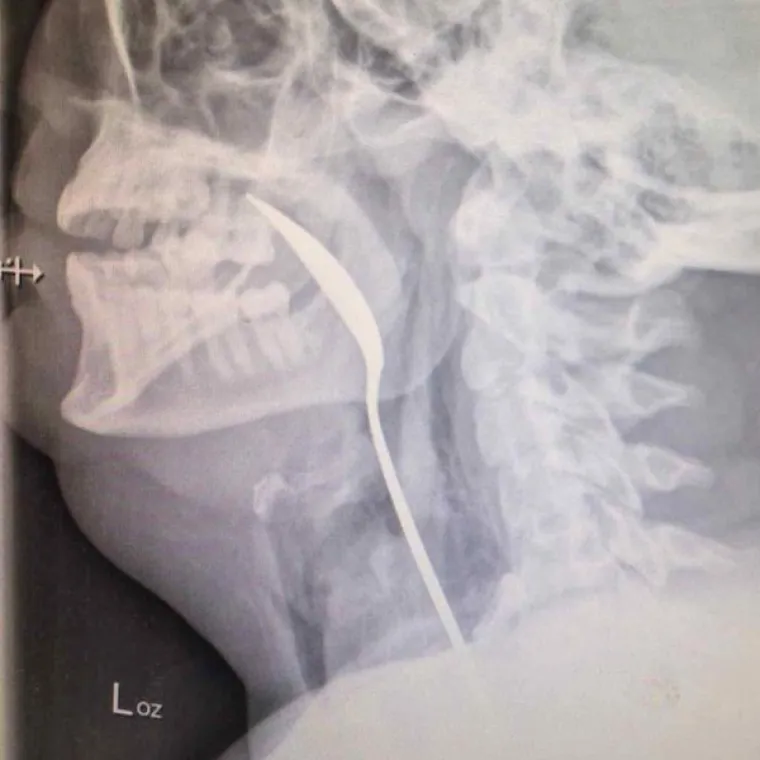

UGURALI U SEBE SVAKAKVA ČUDA, OD BOCA DO TEŠKE ARTILJERIJE: Što je ljudima na pameti kad se dovedu u ovu situaciju?

Žlica.